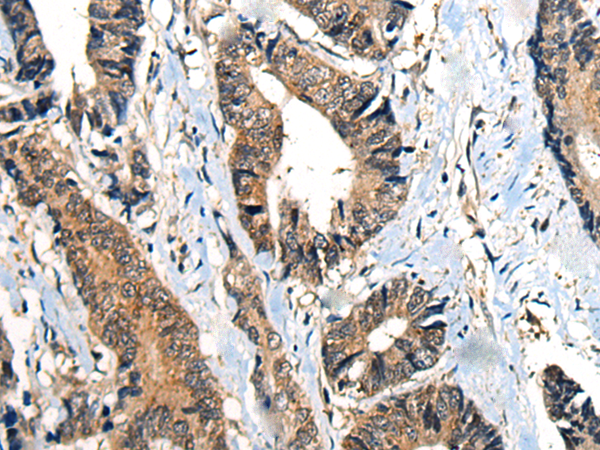

The image is immunohistochemistry of paraffin-embedded Human colorectal cancer tissue using P12955(BMPER Antibody) at dilution 1/40. (Original magnification: ×200) |